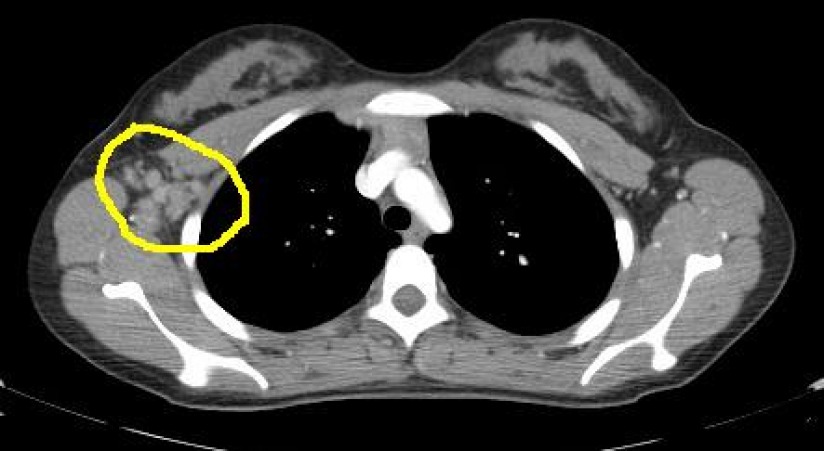

The key finding is, as encircled in this image, a rounded opacity in the right axilla. Here are select CT images demonstrating the presence of several opacities in the right axillary region. The opacities represent lymphadenopathy. Compare with the left axilla where there is no evidence of enlarged lymph nodes.

Diagnosis: Hodgkin's lymphoma (biopsy confirmed). The patient has stage I disease, in other words the disease was limited to a single lymph node group in the right axilla. No additional disease was found in the head, neck, chest, abdomen, or pelvis on CT examination. Clinical examination failed to demonstrate lymphadenopathy in other sites in the appendicular skeleton.